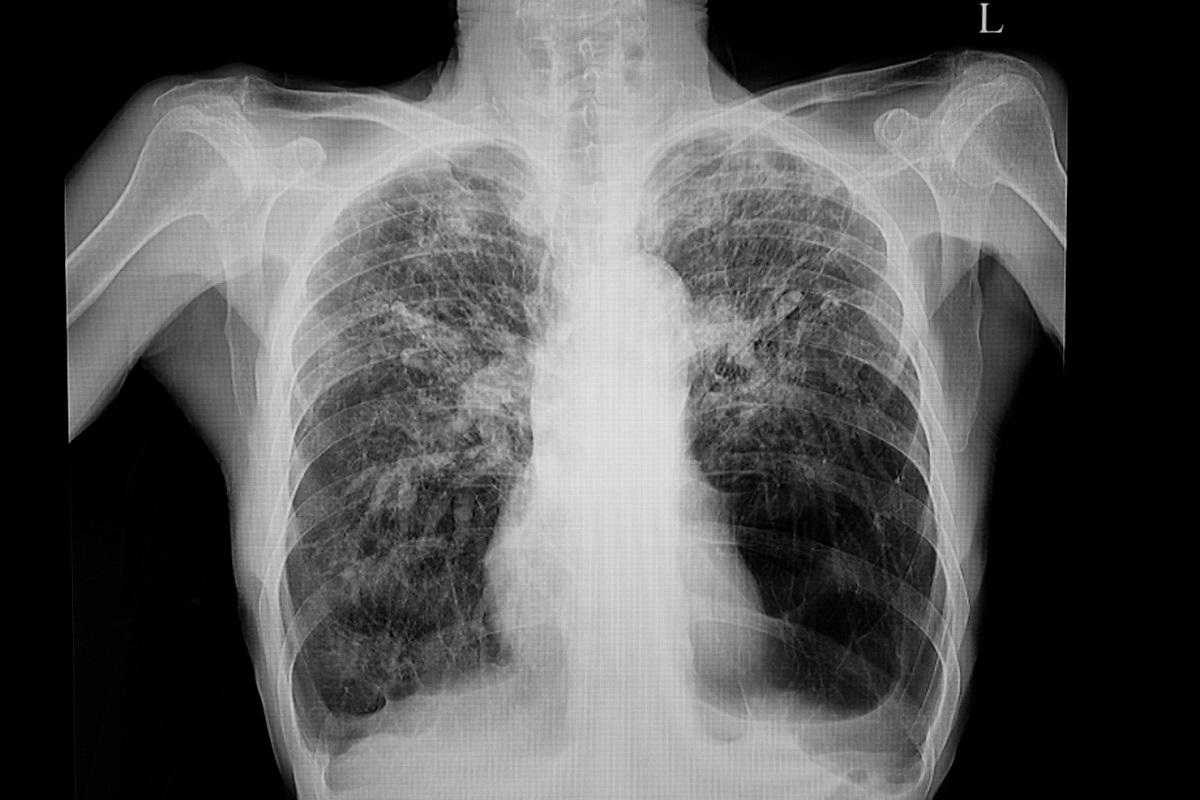

Imaging Studies and Blood Tests

Along with spirometry, chest X-rays or CT scans might be used. They help see lung damage and rule out other diseases. Blood tests can also find other conditions that might be causing COPD-like symptoms.